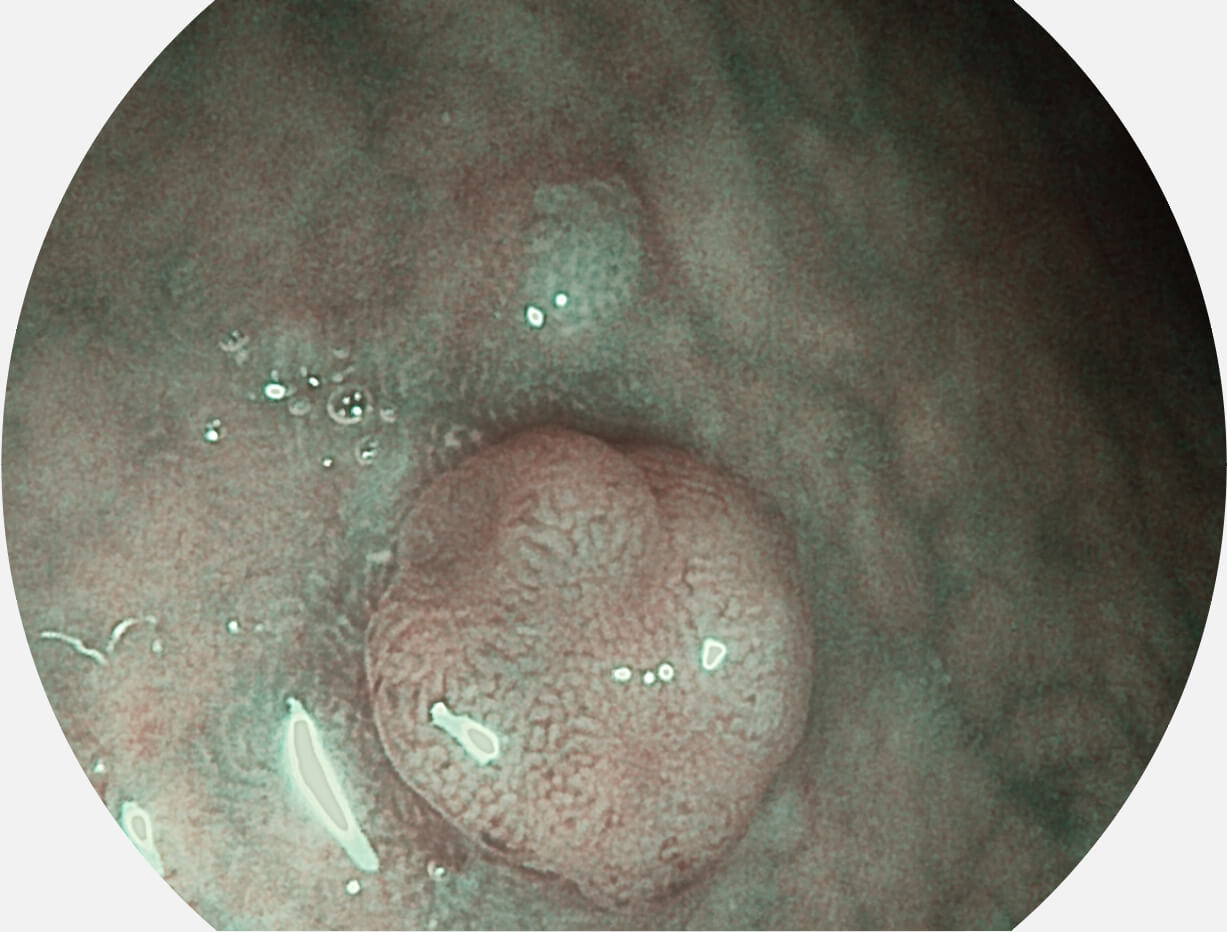

图像具有高亮度、高黏膜血管颜色对比度的特点,且不改变粘液、食物残渣、粪便的基本颜色,可在中远景下进行观察,助力消化道早期疾病的诊断。

Versatile Intelligent Staining Technology, VIST

强调浅层黏膜结构的同时,保证照明亮度和提升浅层微血管与中层血管颜色对比度,病变边界更清晰。

采用光路合束技术,光谱自由度高,实现了更丰富的照明模式,染色模式SFI及VIST,从远景到近景,助力消化道早期疾病诊断。